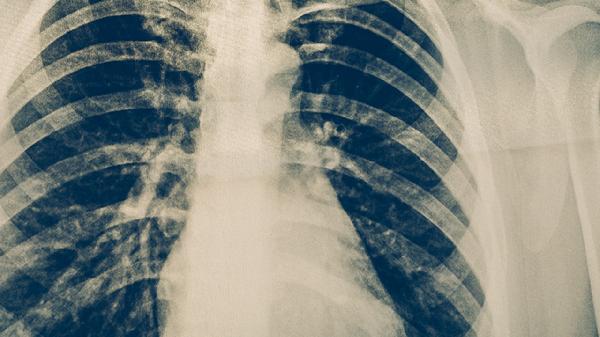

肺结核药物可能引起哮喘发作,但概率较低。抗结核药物中的异烟肼、利福平等可能诱发过敏反应或支气管痉挛,与个体过敏体质及药物代谢差异有关。需结合患者既往哮喘病史、药物使用情况综合评估风险。